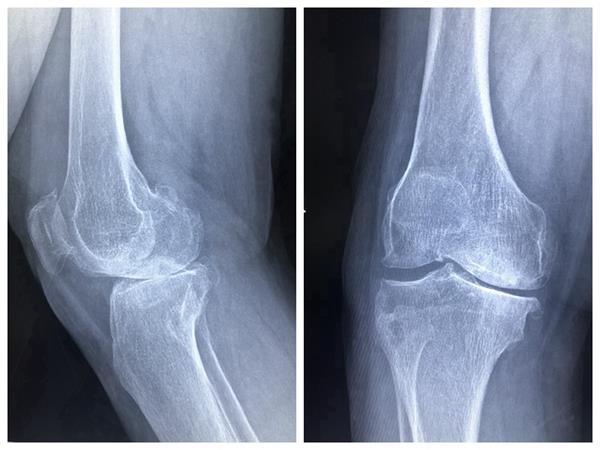

患者右膝关节术前、术后伸屈位放射影像

一位66岁的女性患者,右膝骨性关节炎终末期,经过长期保守治疗无效,深受右膝病痛折磨,坐着轮椅由家人推着入住寿县人民医院骨科。科室主任刘本阳组织医师团队开展讨论,根据患者临床表现,结合多项检查,确定人工膝关节置换为首选治疗方法,并择期手术,为患者成功置换全膝人工膝关节。经过精心治疗护理,患者术后第四天下床活动,术后第七天出院回家康复休养。